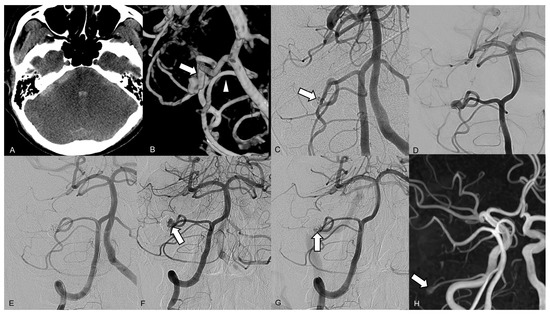

On admission computed tomography (CT), a diffuse subarachnoid hemorrhage was revealed with a predominance of distribution in the right cerebellopontine angle cistern, and a small intraventricular hemorrhage was noted (Figure 2A). Brain CT angiography showed a small contrast pooling near the tumor without a definite connection to the regional vascular structure. Diagnostic catheter angiography revealed a lobulated wide-neck aneurysm arising from the right distal AICA at a meatal segment (Figure 2B). The aneurysm was located at a nonbranching site. A robust right AICA, with a diameter larger than that of the ipsilateral posterior inferior cerebellar artery (PICA), stemmed from the right AICA–PICA complex. Subsequently, endovascular therapy was attempted under general anesthesia. After positioning a 6 Fr guiding catheter in the right vertebral artery, we placed a Headway 17 microcatheter (MicroVention, Aliso Viejo, CA, USA) with a preshaped tip angle of 90° into the aneurysmal lumen over a microwire. Endosaccular coil embolization was performed using five coils, successfully preserving the parent artery and leaving a tiny remnant portion of the neck (Figure 2C). The patient was discharged without any neurologic deficits. Follow-up TOF MR angiography and conventional angiography 3 months after the endovascular procedure revealed recanalization of the coiled pseudoaneurysm, with regrowth of the aneurysm sac from the residual neck (Figure 2D). The second endosaccular coil embolization was performed in the same manner, resulting in complete occlusion of the recurred sac on final angiography (Figure 2E). Thereafter, retreatment was performed due to recanalization of the pseudoaneurysm 30 months after the first embolization (Figure 2F,G). No ischemic complications occurred after either endovascular treatment. Since the final embolization, the patient has been undergoing TOF MR angiography check-ups annually, and a 3-mm small remnant sac has remained stable without changes for 4 years (Figure 2H).

Figure 2.

Brain images from a 42-year-old male who presented with a sudden onset of mental deepening. (A) The axial brain computed tomography scan on admission shows a subarachnoid hemorrhage, predominantly distributed in the right cerebellopontine angle cistern, and a small intraventricular hemorrhage. (B) A three-dimensional reconstruction of the right vertebral artery angiogram reveals a lobulated wide-neck aneurysm arising from the right distal anterior inferior cerebellar artery (AICA) within a meatal segment. The right AICA (arrow) was larger than the posterior inferior cerebellar artery (arrowhead). (C) The right vertebral artery angiogram performed immediately after the endosaccular embolization shows a tiny remnant portion of the neck (arrow). (D) The 3-month follow-up angiograph shows major recanalization at the superior part of the coiled aneurysm. (E) The final angiogram after the second coil embolization shows complete occlusion of the pseudoaneurysm, with preserved distal AICA flow. (F) The 2-year follow-up angiograph shows major recanalization (arrow) at the base of the coiled pseudoaneurysm. (G) The final angiogram after the third coil embolization shows near complete occlusion of the pseudoaneurysm, with a tiny remnant lesion (arrow) at the base. (H) Follow-up magnetic resonance angiography, 4 years after the final embolization, shows a small remnant sac (arrow) at the base of the coiled pseudoaneurysm.